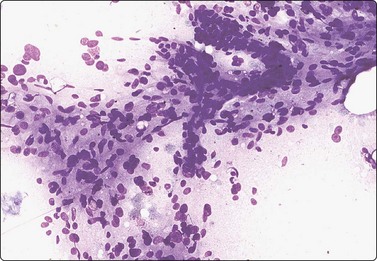

Extra-adrenal paraganglioma (Fig. 12.40)133,134

Extra-adrenal paraganglioma of the sympathetic system of the retroperitoneum down to the pelvic floor is a rare tumor. It is often functional and often malignant. Paragangliomas of the parasympathetic system of the head and neck with a similar cytomorphology are described in Chapter 4. A case of malignant metastasizing paraganglioma of the retroperitoneum is illustrated in Figure 12.40. Intranuclear inclusions are sometimes a feature of this tumor.133

image

Fig. 12.40 Paraganglioma; malignant, comparison with thyroid carcinoma

(A) Paraganglioma; loose cluster of cells with microfollicular groupings; small round dark relatively uniform nuclei; indistinct cytoplasm; fine cytoplasmic granulation not evident on photograph; (B) Metastasis of thyroid follicular carcinoma to retroperitoneal lymph node (MGG, HP); (C) Tissue section from the same case as in (A) (H&E, IP).

A 40-year-old man presented with a large palpable retroperitoneal mass. CT-guided FNB was done as one of the initial investigations and smears showed moderate numbers of cells, single and in loose acinar/follicular clusters resembling thyroid follicular epithelial cells. Nuclei were uniformly round and relatively small and showed moderate anisokaryosis. The nuclear chromatin was granular and evenly distributed; nucleoli were indistinct. The cytoplasm was pale, without distinct cell borders. Many cells showed a fine red cytoplasmic granularity (MGG). The overall pattern suggested a neuroendocrine tumor (Fig. 12.40A). The differential diagnosis included paraganglioma as well as other neuroendocrine tumors such as carcinoid and pheochromocytoma, but also metastasis of follicular thyroid carcinoma and of low-grade renal cell carcinoma. Surgical biopsy confirmed the diagnosis of paraganglioma. Serum catecholamines were not significantly raised, but abundant neurosecretory granules were demonstrated by EM. There were widespread metastases, and the patient died 4 months later.

The striking similarity between the cytology of thyroid carcinoma and that of paraganglioma is illustrated by an FNB smear of a para-aortic lymph node metastasis in a case of follicular carcinoma of the thyroid (Fig. 12.40B). The distinction between paraganglioma and medullary or follicular carcinoma of the thyroid, whether in a primary site in the neck or metastatic to other sites, requires immune marker studies.